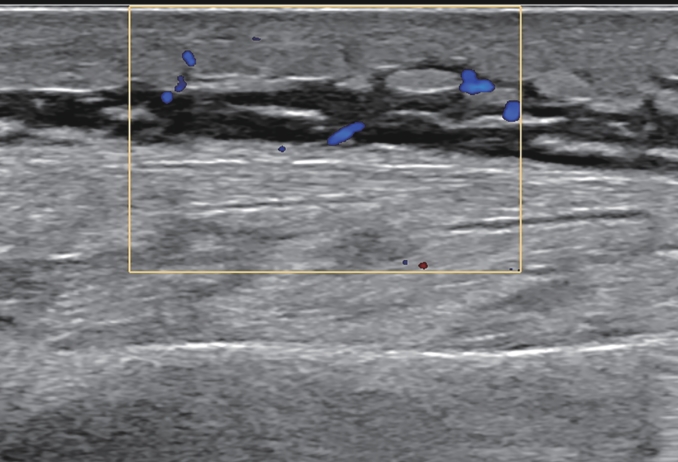

Correlation between liver fibrosis degree and carotid plaque in patients with lean metabolic dysfunction-associated fatty liver disease

Shuai ZHANG, Shoulu JIN, Wanqing LI, Xijing SHI, Hao LIANG, Hao DONG, Dailong LU, Ying ZHU, Xiaoxing XIANG, Jun LIU

2026, 42(2): 319-325. DOI: 10.12449/JCH260212

Abstract:

Objective  To investigate the association between noninvasive liver fibrosis markers and carotid plaque (CP) in patients with lean metabolic dysfunction-associated fatty liver disease (MAFLD), and to provide a basis for screening high-risk populations.  Methods  A total of 957 patients with lean MAFLD who underwent physical examination in Subei People’s Hospital from January 2021 to June 2023 was enrolled as the observation cohort, with the presence or absence of CP as the outcome, and fibrosis-4 (FIB-4) index and nonalcoholic fatty liver disease fibrosis score (NFS) were used to assess liver fibrosis degree. The independent-samples t test was used for comparison of normally distributed continuous data between two groups, and the Mann-Whitney U test was used for comparison of non-normally distributed continuous data between two groups; the chi-square test was used for comparison of categorical data between two groups. The multivariate logistic regression analysis, the restricted cubic spline analysis, the receiver operating characteristic curve, and the mediation effect analysis were used to investigate the association between liver fibrosis degree and CP.  Results  The prevalence rate of CP was 36.6% in the lean MAFLD population. Compared with the non-CP group(n=607), the CP group (n=350) had a significantly higher proportion of male patients, a significantly higher proportion of patients with smoking/diabetes/hypertension, and significantly higher levels of age, creatinine, blood urea nitrogen, triglycerides, fasting blood glucose, aspartate aminotransferase, aspartate aminotransferase/alanine aminotransferase ratio, NFS, and FIB-4 index, as well as significantly lower levels of platelet count and albumin (all P<0.05). The multivariate logistic regression analysis showed that after adjustment for confounding factors, FIB-4 index (odds ratio[OR]=2.979, 95% confidence interval[CI]:2.141 — 4.219, P<0.001) and NFS (OR=1.747, 95%CI: 1.499 — 2.046, P<0.001) were positively correlated with CP. Both FIB-4 index and NFS had a good value in predicting CP. Hypertension had a significant indirect effect on the prevalence rate of CP through its impact on liver fibrosis markers, and its mediating effect accounted for 39.5% — 40.8% of the total effect (P<0.001).  Conclusion  In patients with lean MAFLD, NFS and FIB-4 index are significantly positively correlated with the prevalence rate of CP, and they can be used as potential epidemiological predictive indicators. Liver fibrosis markers may play a mediating role in the association between hypertension and CP. Interventions targeting hypertension and liver fibrosis markers may help to prevent and delay the progression of CP.